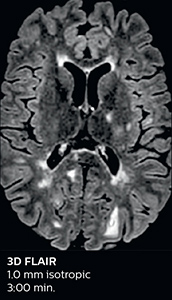

Fast MS protocol with optional sequences

The abbreviated MS protocol for brain is only around 9 minutes, so in case of suspected multiple sclerosis, one or two more advanced sequences may be added, such as PSIR (phase sensitive inversion recovery) or susceptibility-weighted sequences to help us make more confident diagnoses in these inflammatory cases.

In this example, the optional 3D multishot susceptibility weighted sequence with 0.6 mm isotropic voxels is 2 lesions with a central vein sign (arrows) and one lesion with a phase-rim sign (arrowhead). The total scan time, including SmartBrain and axial PD/T2 3mm, is 11:10 min. and is 18:30 min. with the optional 3D PSIR and 3D SWI multishot included.

3D TFE T1

3D FLAIR

DWI image

3D T1w TSE Gd

3D PSIR

3D SWI

“In multiple sclerosis patients, we increasingly include a multishot susceptibility sequence [3] in our routine cases, thanks to the shorter scan times. Our abbreviated MS protocol for brain is around 8 to 9 minutes, so we can ask for one or two additional sequences to visualize the central veins, or to get an additional contrast to better depict posterior fossa lesions. In cases of white matter lesions of unknown significance on FLAIR images, for example when we see high signal hyperintensities in the brain, we can add on more advanced sequences such as PSIR (phase sensitive inversion recovery) or susceptibility-weighted sequences to help us in distinguishing between MS and nonspecific or vascular abnormalities in these inflammatory cases.”